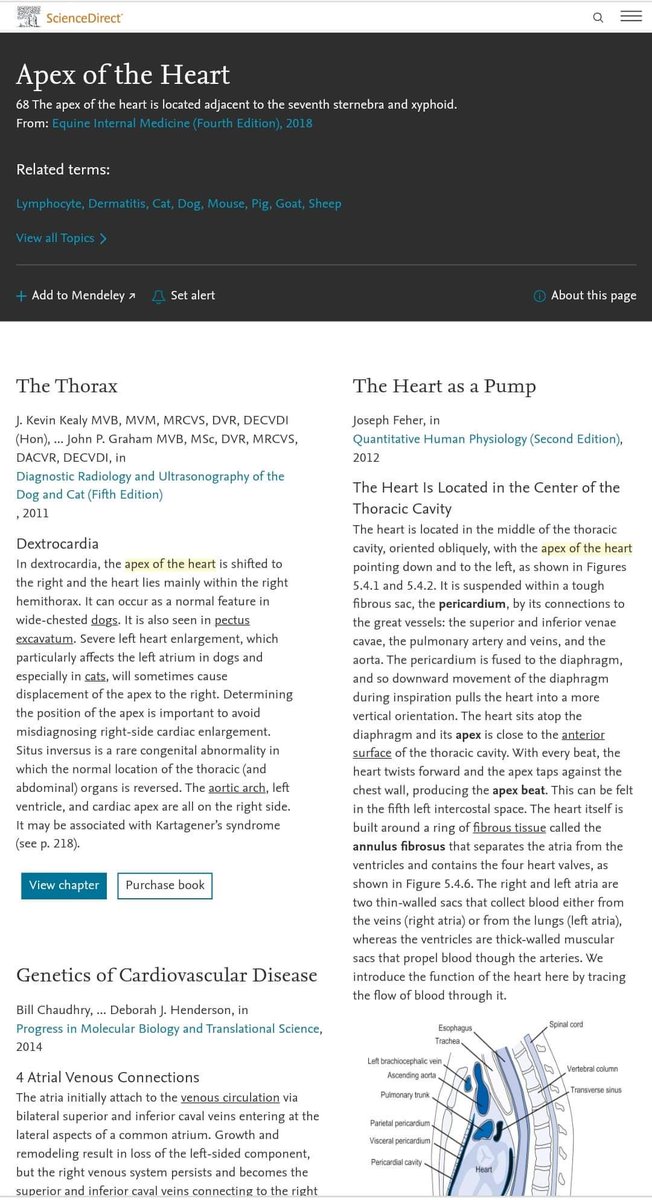

شاهد موضع القلب هنا ؟

تم رسمه فى المنتصف وليس جهة اليسار الحقيقة وبالرغم من بدائية الرسم إلا أن مكان القلب صحيح تمامًا .

لذلك معلومة أن القلب فى جهة اليسار هي معلومة خاطئة والتصحيح هو أن القلب البشرى يقع فى المنتصف خلف عظمة القص مع بعض الميل جهة اليسار عند معظم الأشخاص وليس جميعهم.

شاهد موضع القلب هنا ؟

تم رسمه فى المنتصف وليس جهة اليسار الحقيقة وبالرغم من بدائية الرسم إلا أن مكان القلب صحيح تمامًا .

لذلك معلومة أن القلب فى جهة اليسار هي معلومة خاطئة والتصحيح هو أن القلب البشرى يقع فى المنتصف خلف عظمة القص مع بعض الميل جهة اليسار عند معظم الأشخاص وليس جميعهم.

وقمة القلب الموجودة فى الجهة اليسرى فى الأغلب كما ذكرنا قريبة من السطح الأمامي للتجويف الصدري و مع كل نبضة، يلتف القلب للأمام و تنقر القمة على جدار الصدر، مما ينتج نبضات القمة.

وقمة القلب الموجودة فى الجهة اليسرى فى الأغلب كما ذكرنا قريبة من السطح الأمامي للتجويف الصدري و مع كل نبضة، يلتف القلب للأمام و تنقر القمة على جدار الصدر، مما ينتج نبضات القمة.

6- بعد تصحيح المعلومة دعنى أخبرك ما الحكمة لكون قلب الإنسان فى منتصف الصدر ؟

هناك قاعدة تشريحية تنص على أن التكوين يتبع الوظيفة لذلك وجود القلب فى هذا المكان بجانب الرئتين لتبادل الدم يجعل القلب يقوم بوظيفته بصورة أفضل ووجود الرئتين هنا لتكون قريبة من مجرى التنفس وكذلك قريبة من الدماغ.